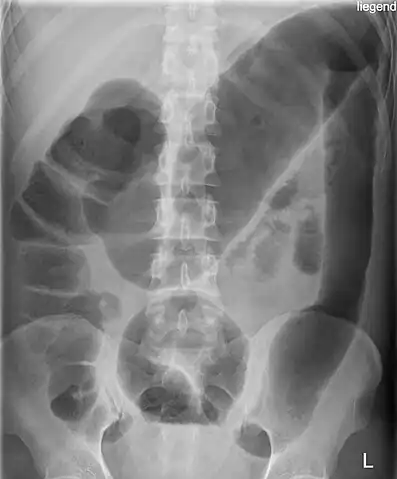

Abdominal X-ray with the features of Air-fluid level can be shown or CT Scan with Contrast can be done if the patient is stable.

-

Toxic megacolon (and an appendiceal-sigmoid fistula). -

Toxic megacolon in a patient with ulcerative colitis: The patient subsequently underwent a colectomy.